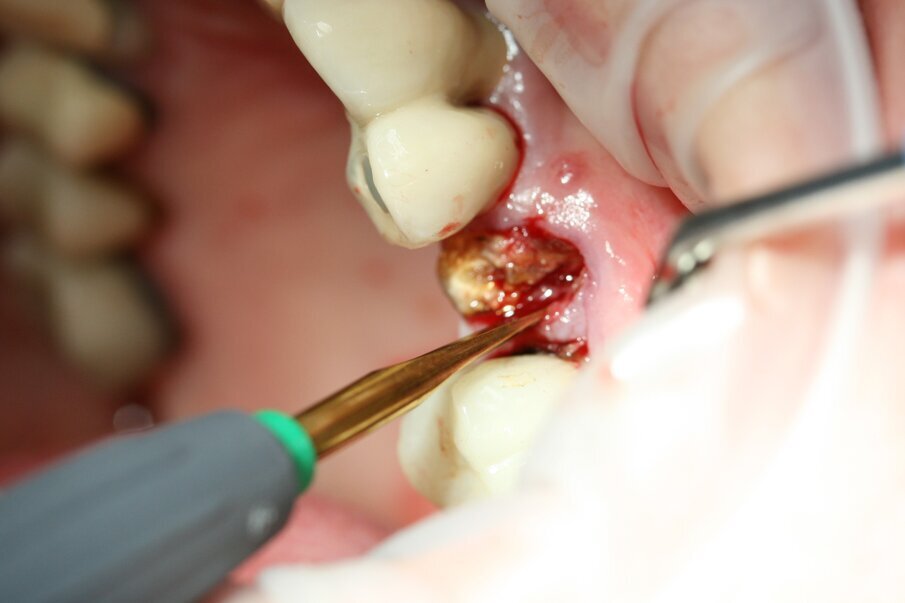

Fig. 7: We continued to luxate with Luxator P1 (straight blade, dark green) until the root felt sufficiently loose.

Luxator P4, with its extremely sharp dual-edge blade, was used at the beginning, followed by Luxator P1 once more space had been created. Although the blades of these sophisticated instruments are reinforced with a titanium coating, they should only be used to cut the periodontal ligament and never to elevate the tooth.